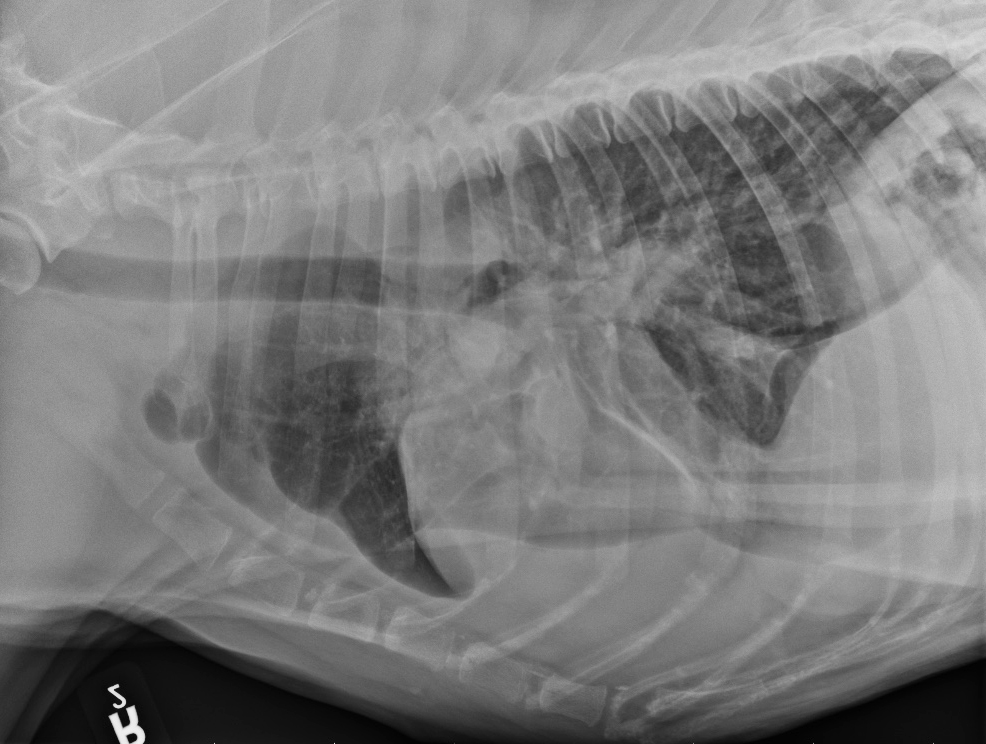

Latérale droite